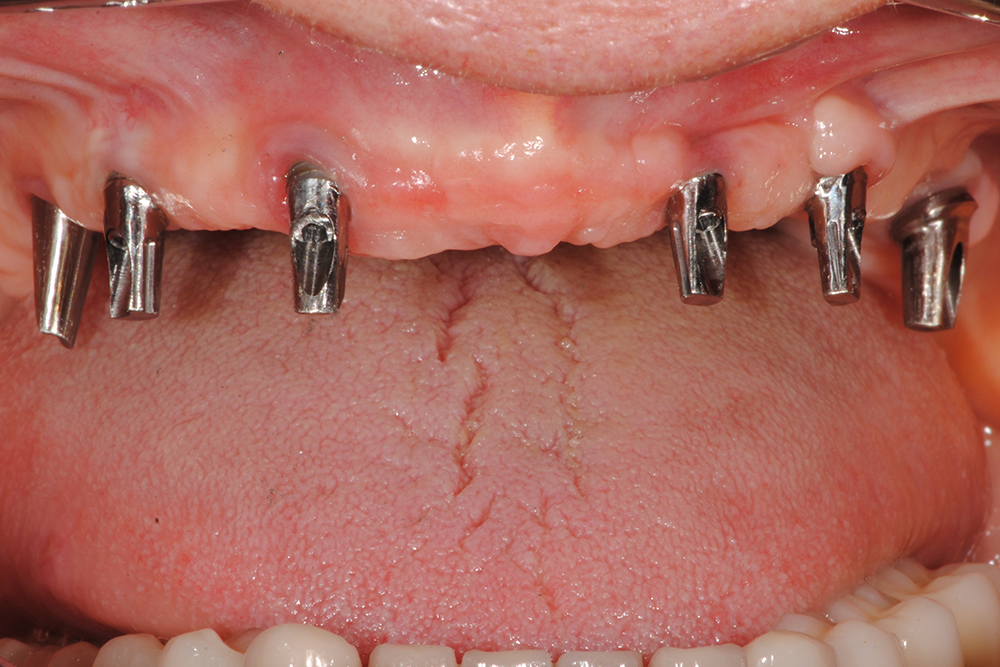

Ripristino dell'arcata superiore atrofica su impianti con ricostruzione estetica in zirconia e ceramica Category: Lavori ImpiantiMaggio 9, 2018Condividi questo ProgettoShare with FacebookShare with TwitterShare with Google+Share with PinterestShare with LinkedInProject navigationPreviousPrevious project:Ripristino dell’arcata superiore atroficaNextNext project:Ripristino dell’arcata superiore ed inferiore